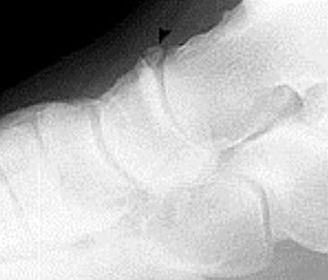

| What type of fracture is this? | Avulsion fracture |